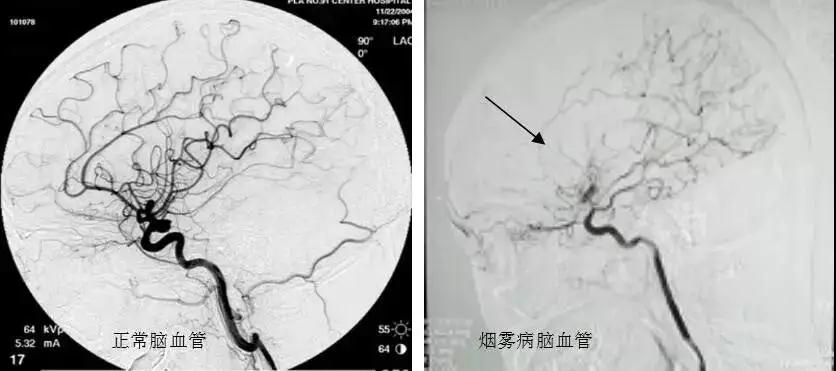

烟雾病属于脑血管病的一种,又称自发性颅底动脉环闭塞症,是以颈内动脉末端及大脑前或中动脉起始部动脉内膜缓慢增厚,动脉管腔逐渐狭窄以至闭塞,脑底穿通动脉代偿性扩张,形成异常毛细血管网为特征的慢性脑血管疾病。因在血管造影中,脑底的异常血管形状酷似吸烟时吐出的烟雾,故称为烟雾病。